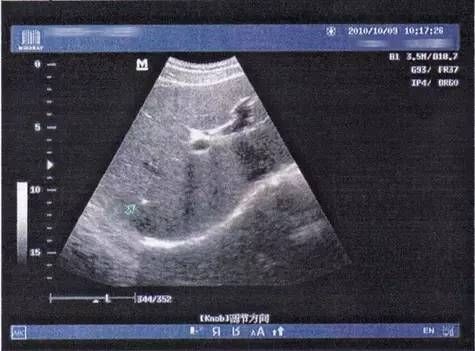

解病

肝胆外科主任张雅敏带领团队为患者制定了个体化的微创治疗方案并且启动了胆管疾病多学科联合诊疗(MDT)。MDT小组先期在X线透视下经皮肤、肝脏建立进入肝内胆管的通道,通过球囊扩张解决胆管狭窄问题;随后利用纤维胆道镜经过逐级扩张后的通道进入肝内胆管,通过胆道镜直视下微爆碎石、取石一次性完成。